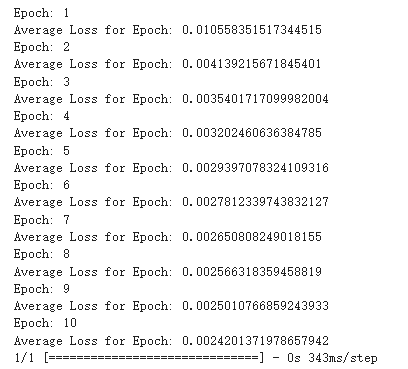

Figure 5. The training process of diffusion model.

By observing the image generated by the diffusion model, it can be observed that it has more and better details, and it only uses 10 Epoch for training shown in Figure 5. It almost perfectly imitates the original image, although it has a huge flaw, that is the generation speed is very slow.

Diffusion Model: While the diffusion model required a mere 10 epochs, its generative process was notably slower. Although this model delivers superior image quality, its prolonged generation time might be a bottleneck in certain applications.